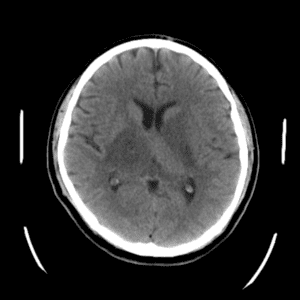

Case #42

Giant cerebral aneurysm